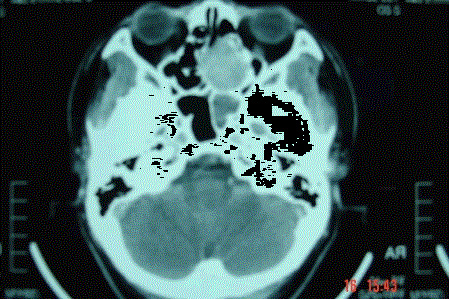

问题 病历摘要: 患者男,37岁,因右鼻塞伴涕中带血4个月入院,患者4个月前始右鼻塞,为间断性,偶有涕中带血,时有流脓性分泌物,并症状渐渐加重。但发病以来患者无头痛、面部麻木和疼痛,无复视及流泪,张口正常。检查:右侧鼻腔总鼻道可见表面光滑、质中、粉红色肿物,触之不易出血。鼻咽黏膜光滑,未见新生物和黏膜糜烂。颈部未及淋巴结肿大。 假如该肿瘤非目前状态,而是已侵犯颅底,如采用鼻窦进路切除该肿瘤,需注意些什么?

选项 A、术后发生脑脊液漏可能为硬脑膜缝合覆盖不严密所致 B、彻底咬除被肿瘤侵蚀的颅底骨质,直至正常的骨结构为止 C、如发现硬脑膜表面不平、色泽改变应加切除 D、尽量将肿瘤整块切除 E、切除怀疑被侵犯的脑膜时,边界应离肿瘤外界至少3cm F、根据术中情况,必要时需颞肌筋膜或人造脑膜修复 G、如发现硬脑膜内层粗糟不平、与脑组织粘连者,应予以保留 H、切除怀疑被侵犯的脑膜时,边界应离肿瘤外界至少3mm